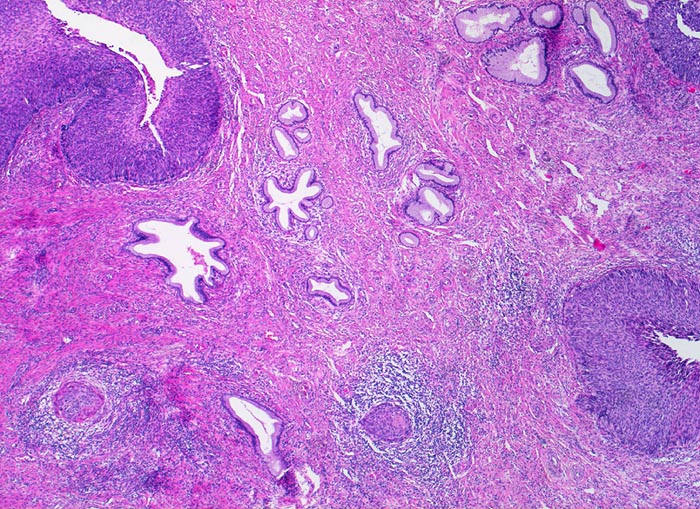

PathoPic ID 3434 - Mikroinvasives Plattenepithelkarzinom, ausgedehntes Cis

Mikroinvasives Plattenepithelkarzinom, ausgedehntes Cis

maligner Tumor

Zervix

Genitalorgane, weiblich

Carcinoma in situ des metaplastischen Plattenepithels in der Umwandlungszone.

Stromainvasion.

PAP V, HPV high risk Typen

Histologie

25